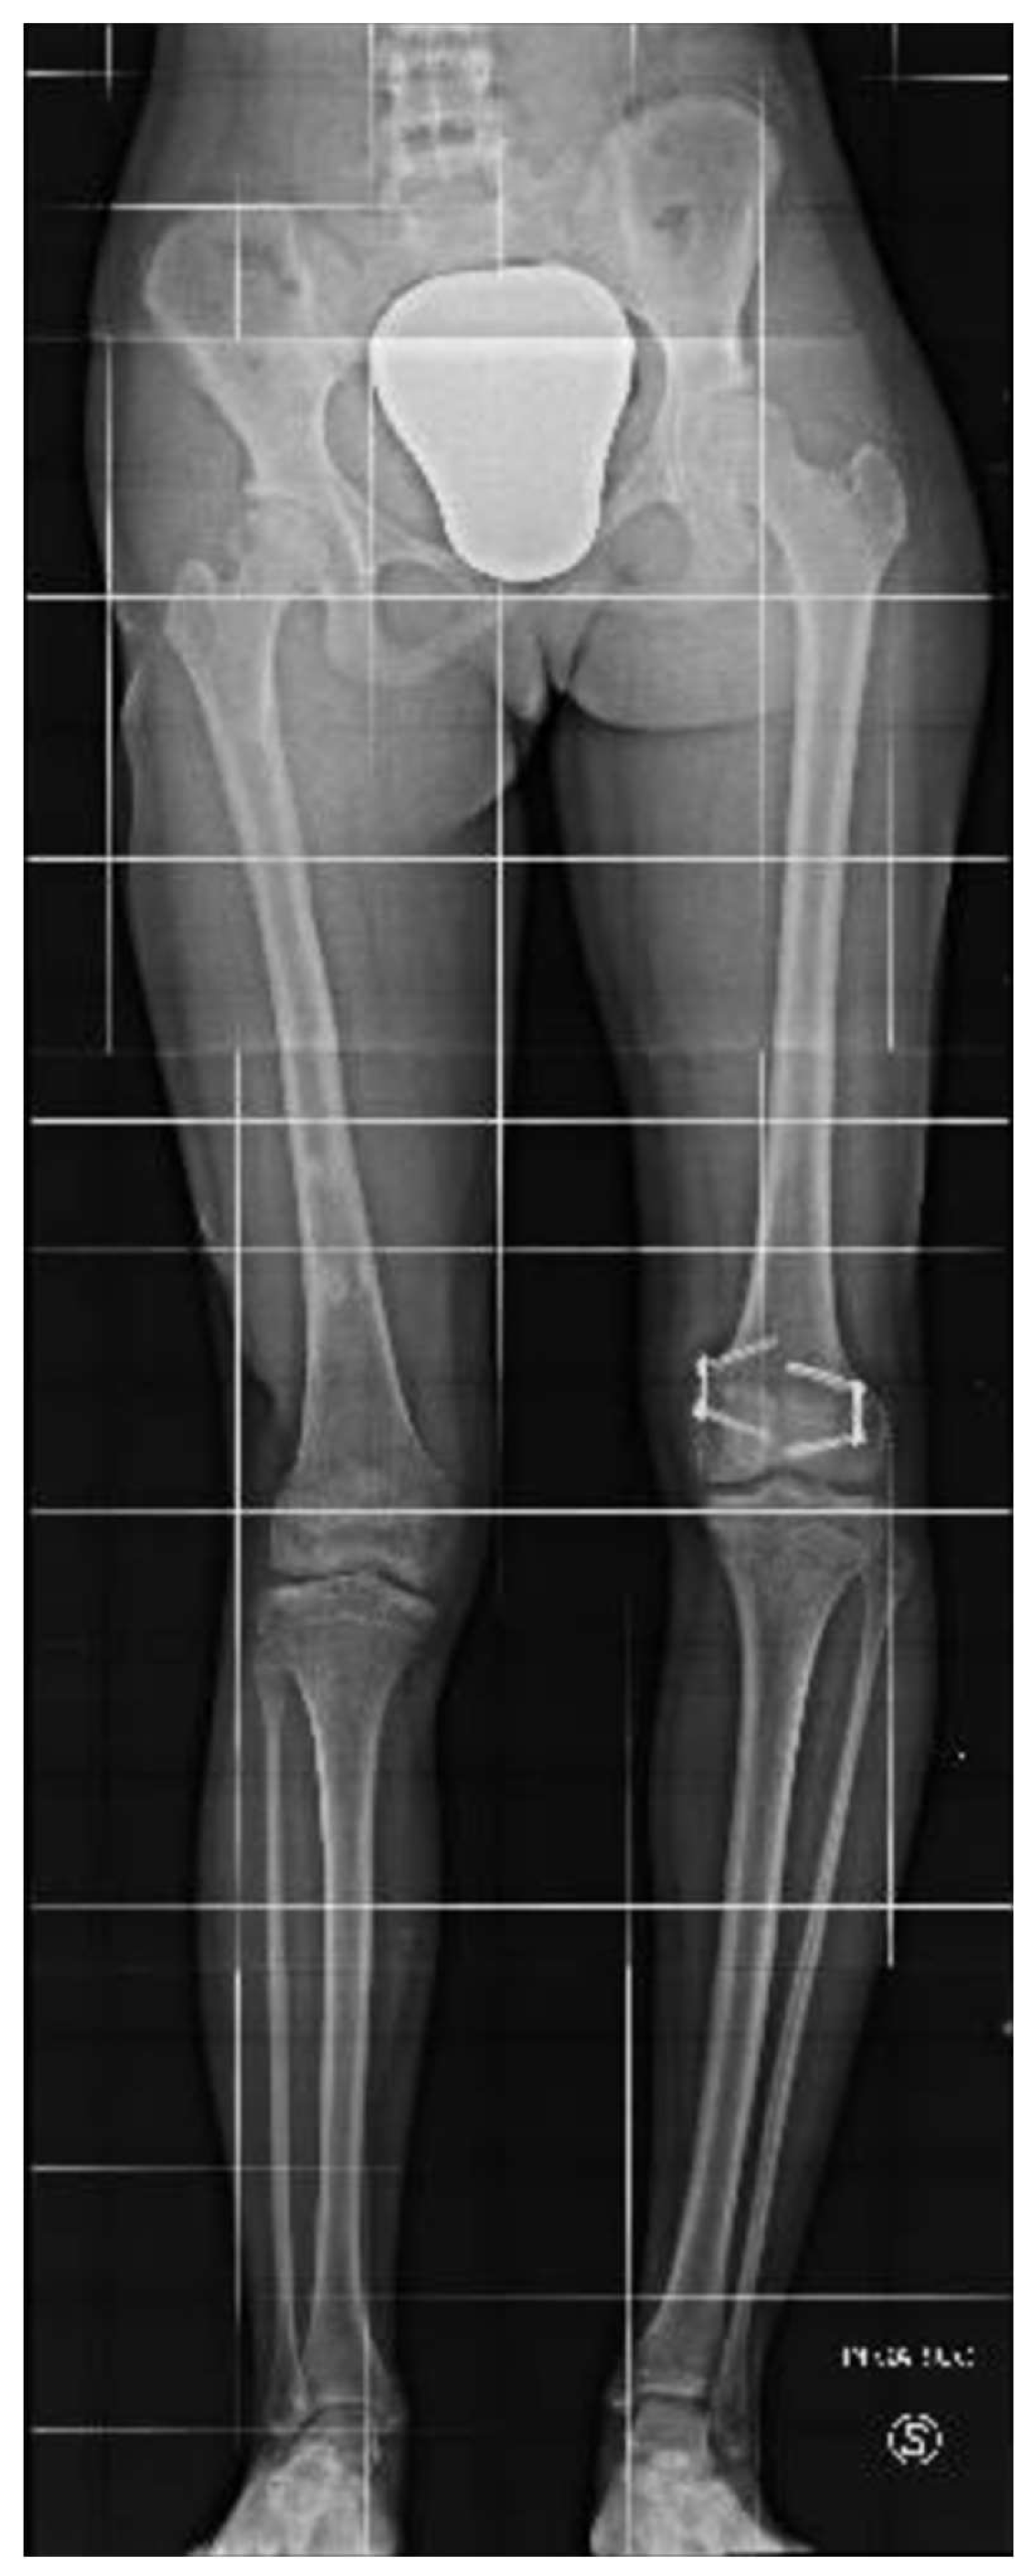

An 8-year-old girl presented to a different hospital with a complaint of leg length discrepancy, right shorter than left. She was brought to local medical attention and promptly diagnosed with congenital femoral deficiency and ipsilateral tibial hypoplasia. At this time, the patient had an acquired leg length discrepancy of 75 mm (femoral 50 mm and tibial 25mm) (Figure 1), she therefore underwent a proximal femoral osteotomy and placement of a LRSTM Orthofix monolateral external fixator to the femur at a different hospital. The procedure was well tolerated with no complications and adequate surgical wound healing. Seven days post-operatively she began the lengthening procedure which consisted of 1/4 turn 4 times per day for a total of 1 mm per day. The patient was followed every two weeks for the first month and then monthly with physical examination and plain film radiographs.

The patient was instructed to start physical therapy for hip and knee range of motion immediately after surgery, while progressive weight-bearing was commenced on the last day of lengthening. At 12 weeks the lengthening goal, 60 mm, was achieved. At 5-months follow up, lower-limb weight-bearing plain radiographs demonstrated that the right femur was within 5 mm of length of the left femur and bone regeneration was visible in the osteotomy gap, however, the study was limited by the inability to fully extend the right knee (Figure 2). Lateral projection radiographs of the right knee showed posterior subluxation of the tibia with respect to the femoral condyles (Figure 3). No action was taken at the time.